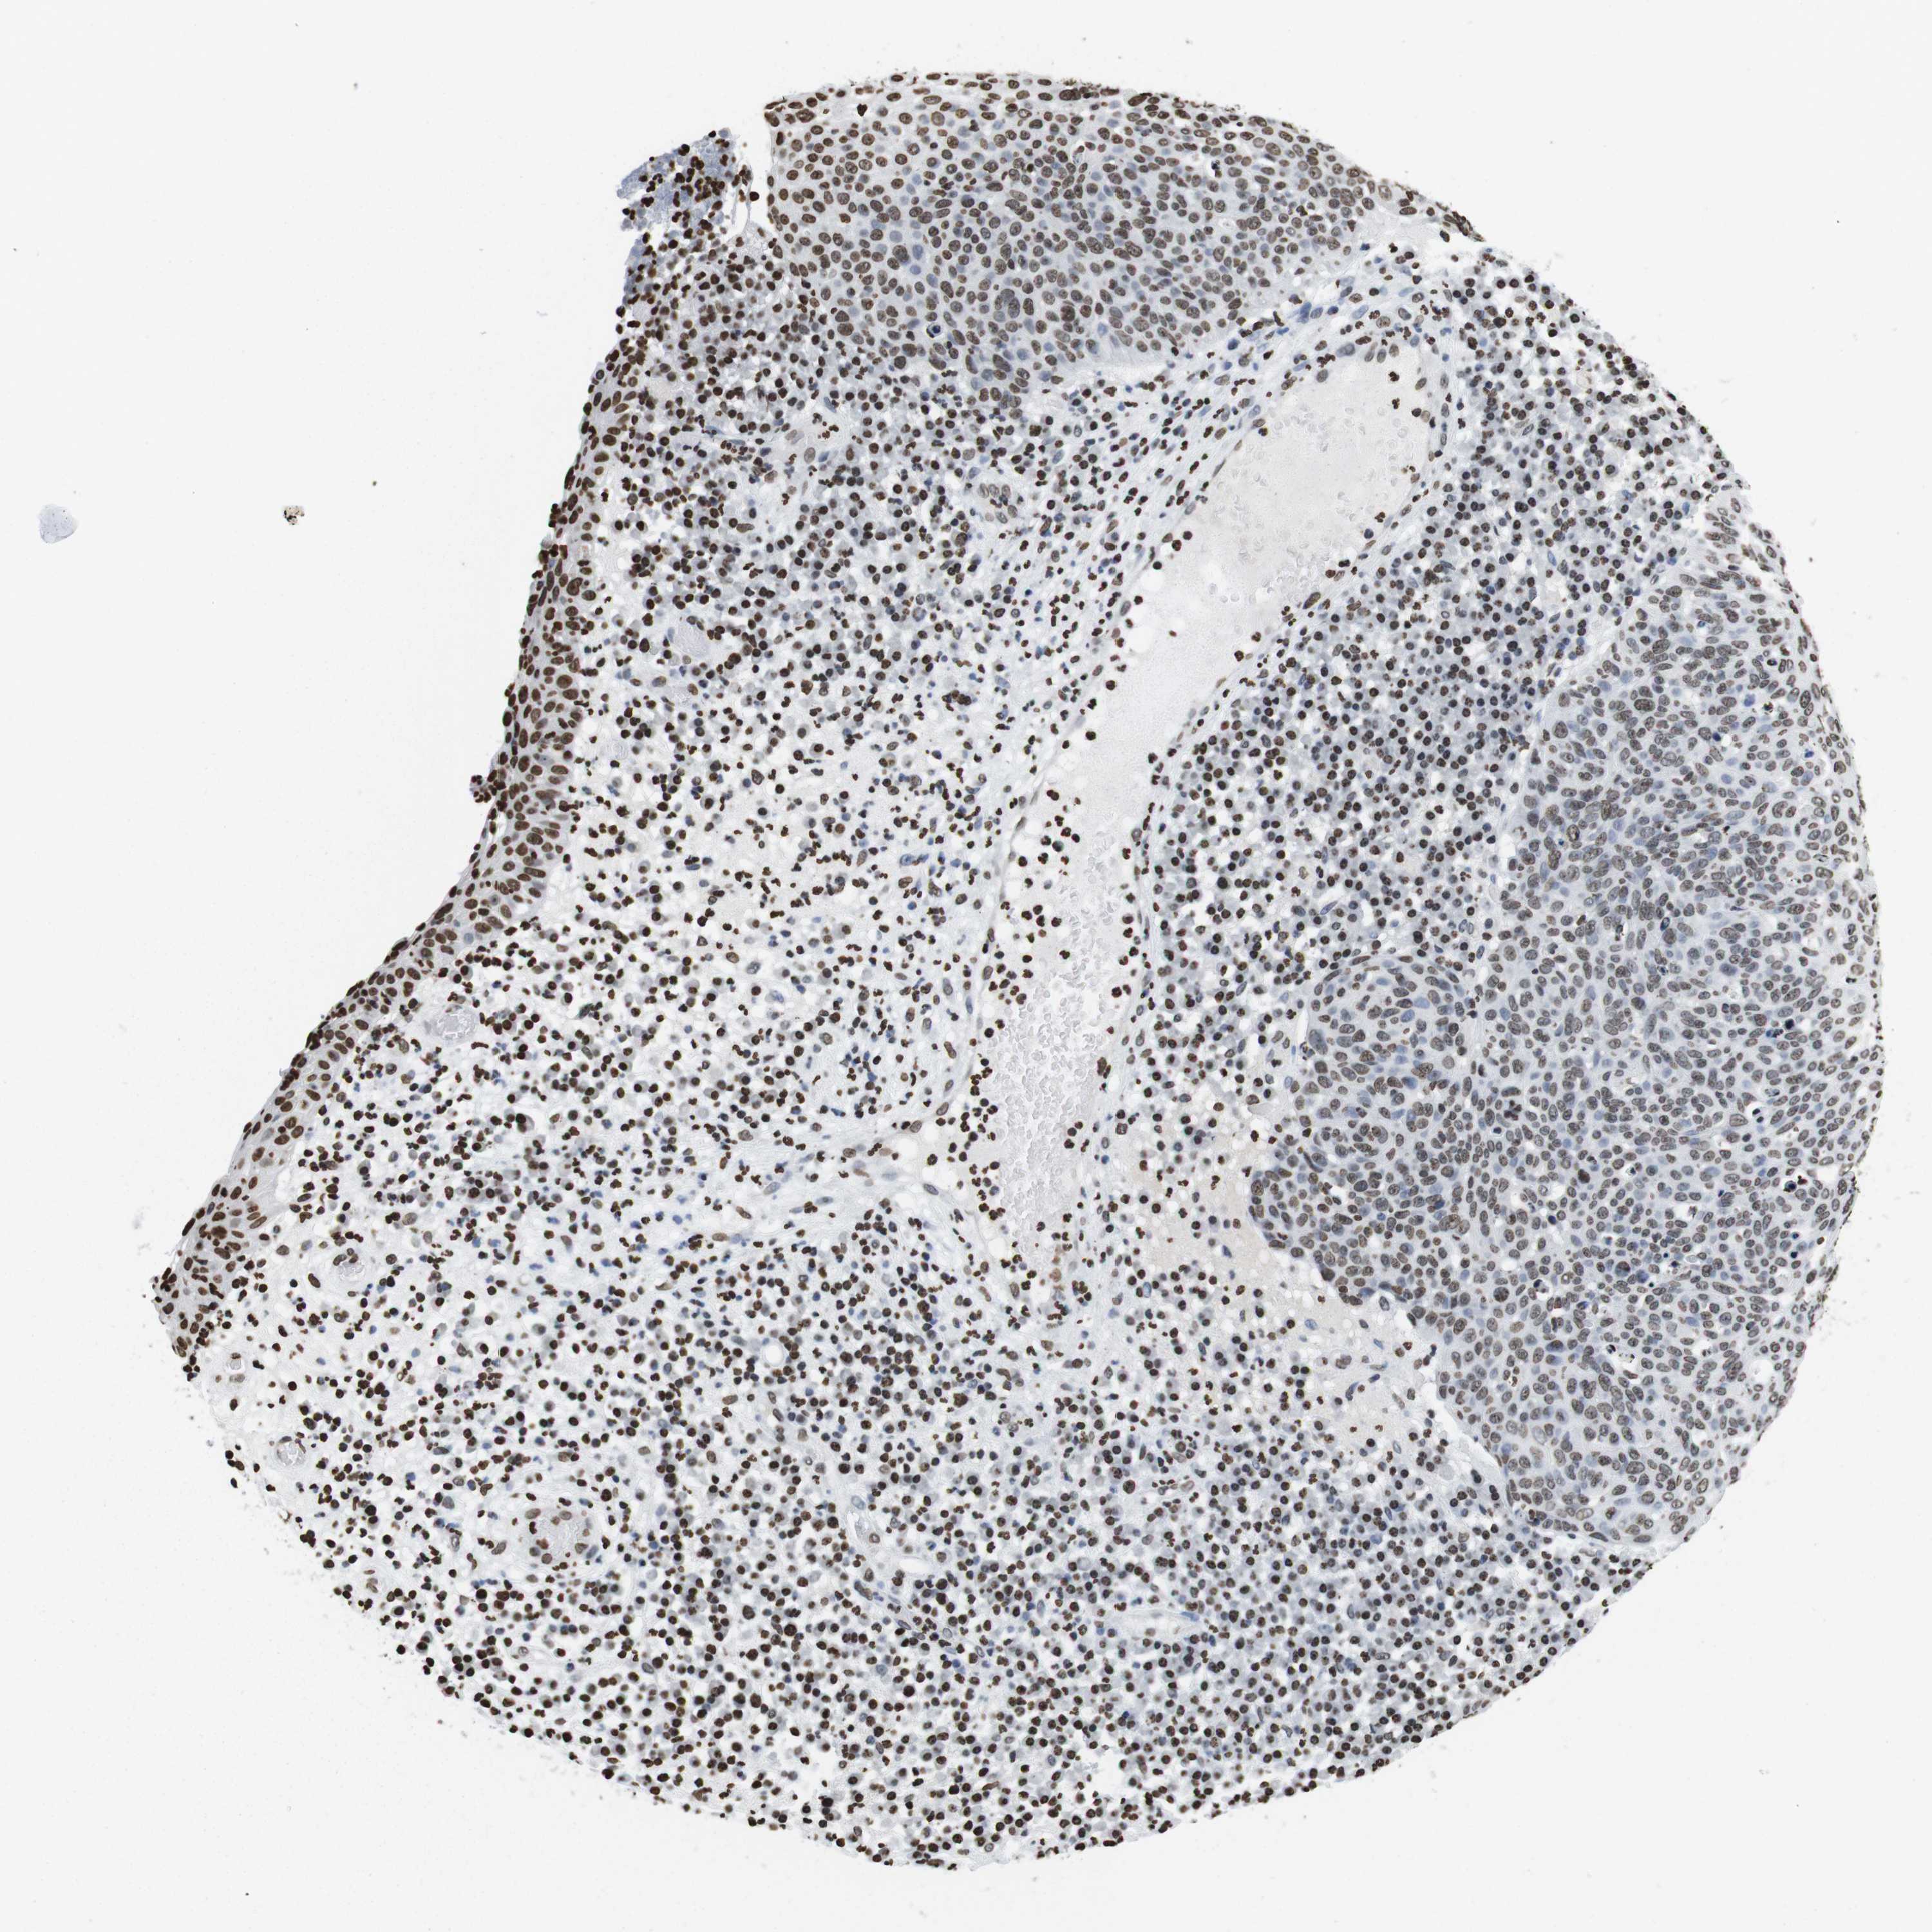

SKIN CANCER - Protein expressioni

A mouse-over function shows sample information and annotation data. Click on an image to view it in a full screen mode. Samples can be filtered based on level of antibody staining by selecting one or several of the following categories: high, medium, low and not detected. The assay and annotation is described here.

Antibody stainingi

Antibody staining in the annotated cell types in the current human tissue is reported as not detected, low, medium, or high, based on conventional immunohistochemistry profiling in selected tissues. This score is based on the combination of the staining intensity and fraction of stained cells.

Each image is clickable and will lead to virtual microscopy that enables deeper exploration of all samples and also displays staining intensity scores, fraction scores and subcellular localization as well as patient and tissue information for each sample.

Antibody HPA015654

Staining

High

Intensity

Strong

Quantity

>75%

Location

Nuclear

Squamous cell carcinoma in situ, NOS

Squamous cell carcinoma, NOS

Basal cell carcinoma

Adnexal tumor, benign